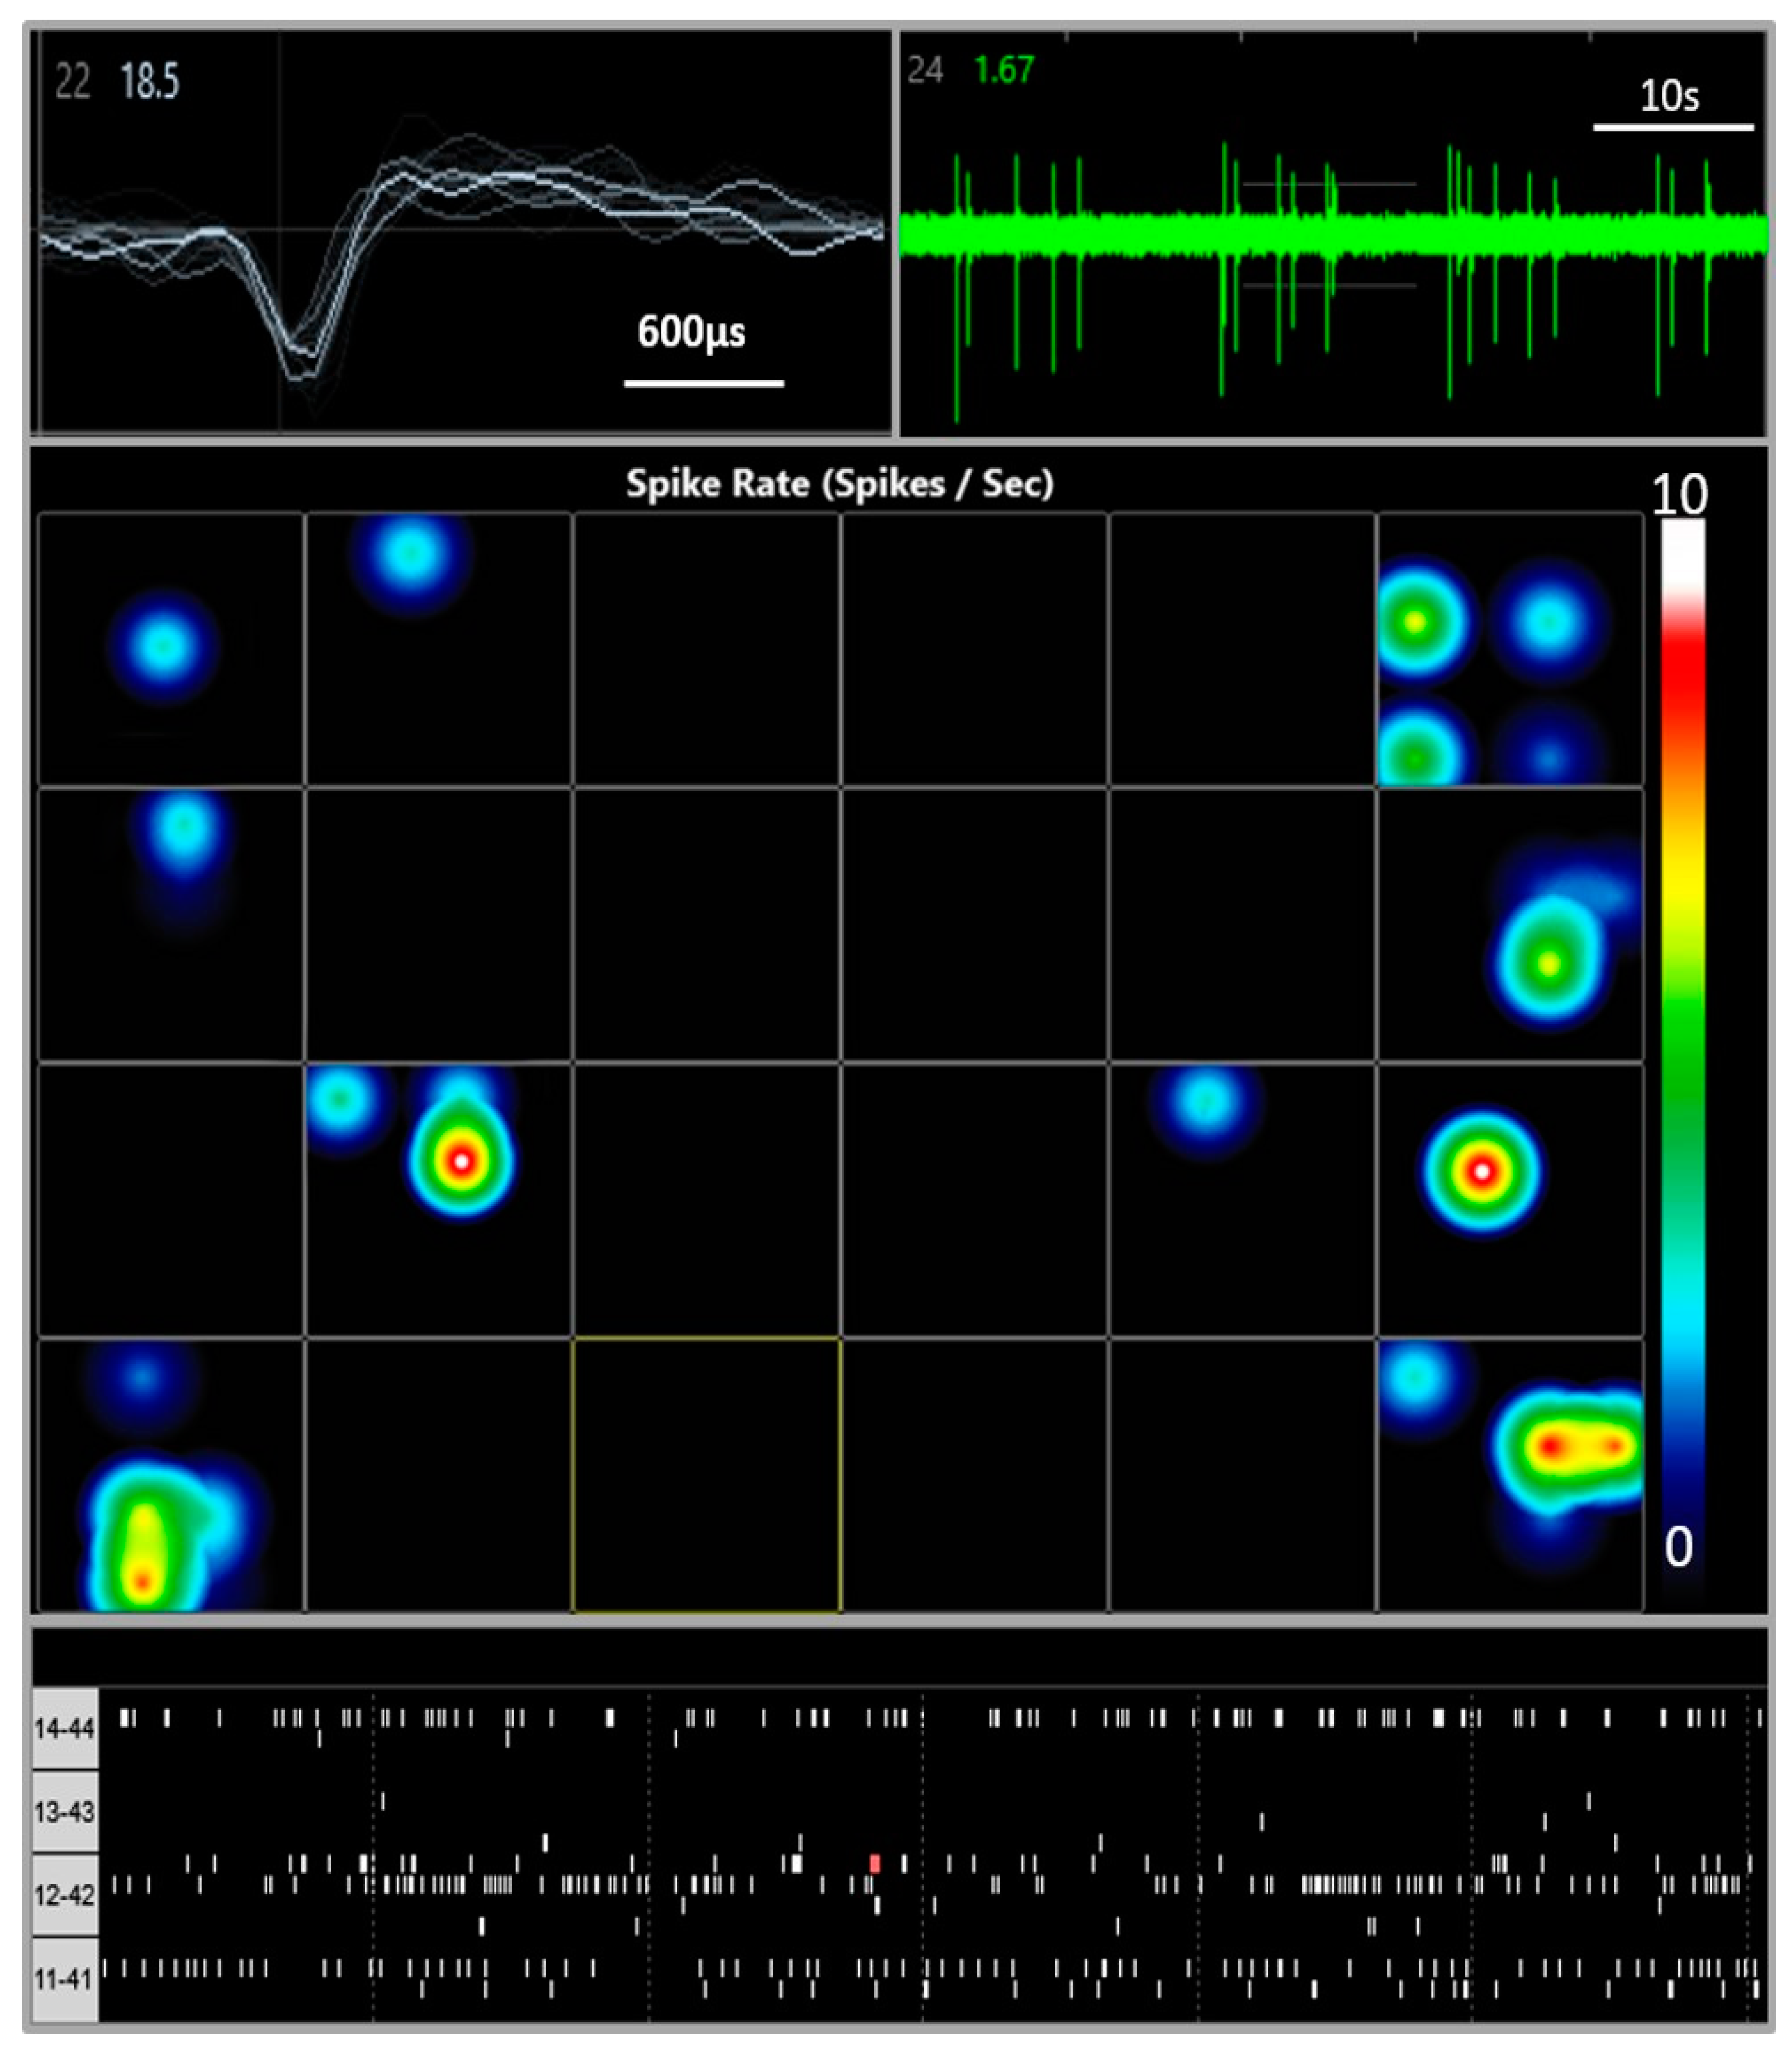

2.3. Multi-Electrode Array Electrophysiology

3.1. Multi Electrode Array